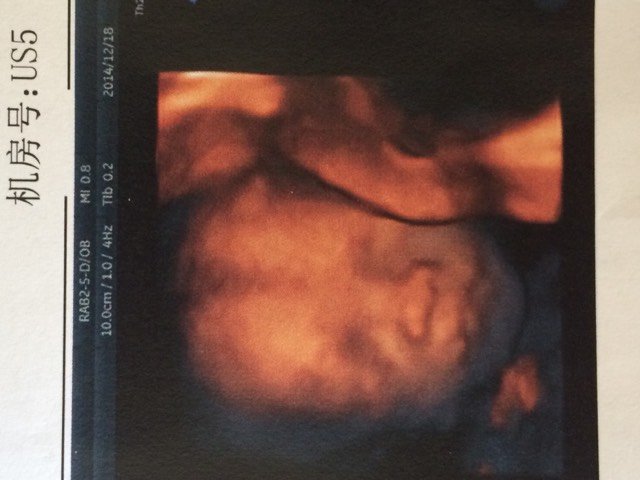

今天去照三维B超宝宝还算配合,医生说比实际孕周偏小一周这问题应该不大吧?看照片宝宝嘴巴上有皱痕应该不是唇裂吧?还没预约拿给医生看有在线医生帮我看看吗?

不会的,有的挂医生会告诉你,这个时候宝宝还没有发育完整,别担心,